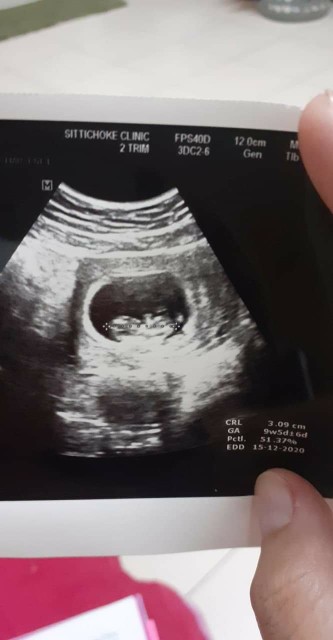

15 ธันวาคม 2563 จ้า😍

บ้านนี้คลอด 15. ธ.ค 63. จ้า